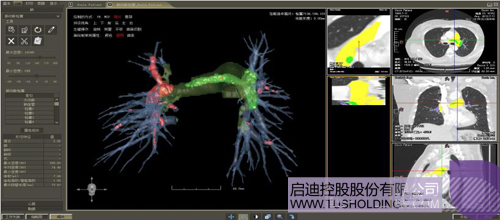

(1)計算/微分幾何用于分析、量化、可視化影像中所變現的各類組織以及病變等形態特征,機器學習主要對影像以及相關病變進行分類等定性分析并輔助一些定量分析,是服務臨床的一個重要模塊或者環節但不是唯一的環節。上述兩者在影像分析中互為補充、彼此增強,構建了神州德信智能影像分析的技術基礎。

(2)在整個智能影像分析中,核心技術建立在對醫學圖像深刻理解的基礎之上,相關幾何分析技術可以對數據進行有效增強和預處理,提升目前深度學習的學習能力、盡可能降低深度學習對樣本規模、多樣性和標注的要求,有效改變當前以深度學習為代表的“人工智能”重在 “人工”而不是“智能”的特點。

完整的三維影像智能分析技術;

完整的三維可視化以及相關建模、幾何分析技術;

肺動脈栓塞輔助診斷